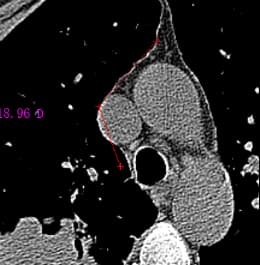

打开图像后,可以使用选择工具对图像进行ROI(感兴趣区域)标注,区域形状可选择直线、矩形、椭圆或多边形,如下图所示。